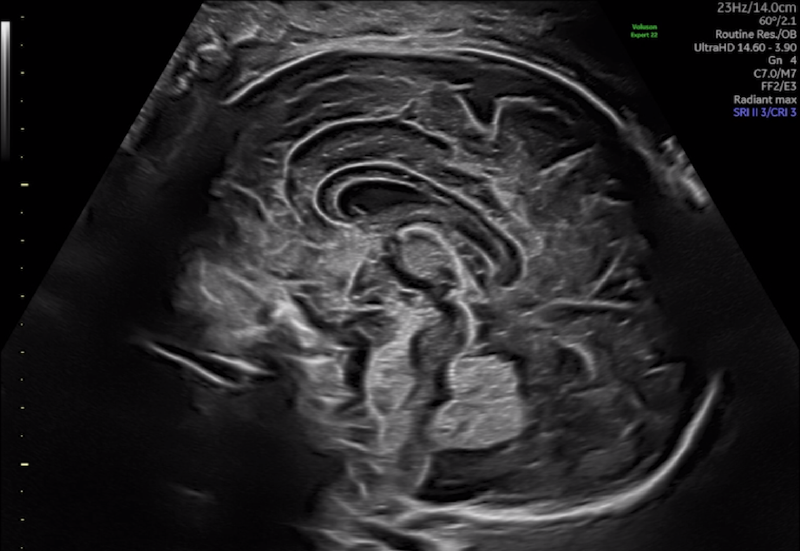

Επικοινωνία Ραντεβού Απαιτούμενες ΕξετάσειςΡαντεβούΡαντεβού, παραπομπή εγκύων και απαιτούμενες εξετάσεις